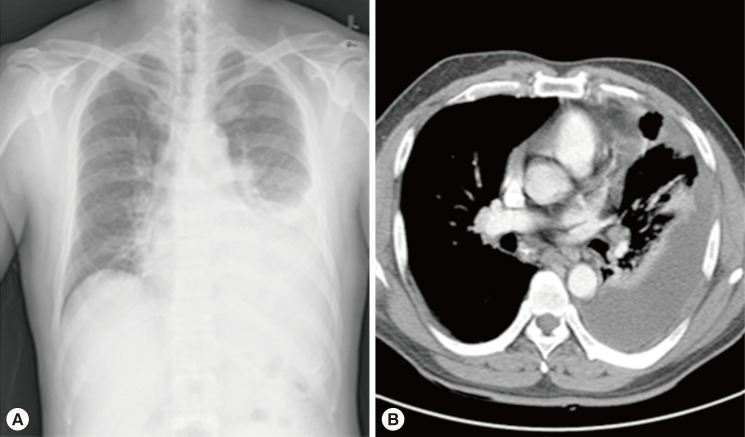

He presented with an acute ill-looking appearance and a body temperature of 38.6℃. Initial laboratory test showed a mildly increased white blood cell count of 12,000/µl with eosinophilia (15%). Blood chemistries were within normal limits. ELISA or immunofluorescence test was used for detecting specific antibodies in serum against Paragonimus westermani, Clonorchis sinensis, and Toxoplasma gondii, and the results were negative. The chest radiograph and CT scan revealed loculated pleural effusion in the left lower lobe (Fig. 1A, B).